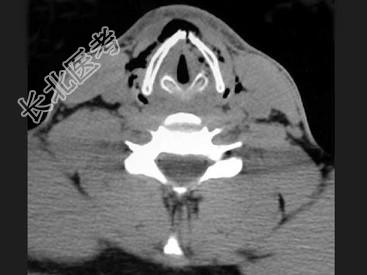

- 多项选择题男,27岁, 开车外出在高速行驶时翻车,呼吸困难, 喉部肿胀,CT检查如图所示, 正确的描述或诊断是 ( )

A、左侧甲状软骨骨折

B、左侧梨状窝软组织肿胀

C、颈部、胸骨下方软组织积气

D、左侧杓状软骨骨折

E、考虑喉、气管破裂